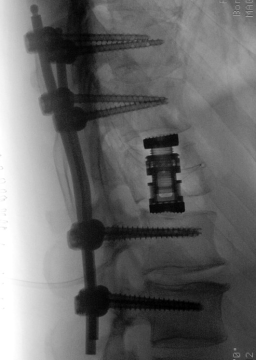

Pacient, ktorý bol privezený v kritickom stave, bol prijatý na pracovisko neurochirurgie v Nemocnici Ružinov, kde postúpil urgentnú operáciu chrbtice. „V prvej fáze sme pristúpili k fixácii chrbtice pomocou titánovej konštrukcie pre stabilizáciu komplexnej zlomeniny a uvoľnili sme utlačené nervové štruktúry dekompresiou." poznamenal MUDr. Peter Hudák, lekár na Neurochirurgickej klinike SZU a UNB.

Po prvej operácii sa začali objavovať známky zlepšovania funkcie dolných končatín. Tento pozitívny vývoj umožnil tímu neurochirurgov pokračovať v liečbe moderným, miniinvazívnym postupom. Po pár dňoch bola

uskutočnená druhá fáza operačného výkonu. „V druhom kroku sme realizovali miniinvazívnu - MISS retropleurálnu korpektómiu stavca L1 – špecializovaný miniinvazívny zákrok, pri ktorom sme odstránili poškodený stavec a obnovili stabilitu chrbtice. Tento prístup je pre pacienta šetrnejší, umožňuje rýchlejšiu rekonvalescenciu a minimalizuje pooperačné komplikácie. Zároveň umožňuje pre pacienta bezpečnú a skorú rehabilitáciu.“ vysvetlil vedúci operatér MUDr. Peter Hudák.